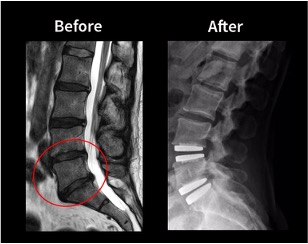

Lumbar disc replacement (also called artificial disc replacement) is a surgical procedure where a damaged disc in the lower spine is removed and replaced with an artificial implant designed to preserve motion. The procedure is typically performed using an anterior approach, meaning the spine is accessed through the abdomen rather than through the back.